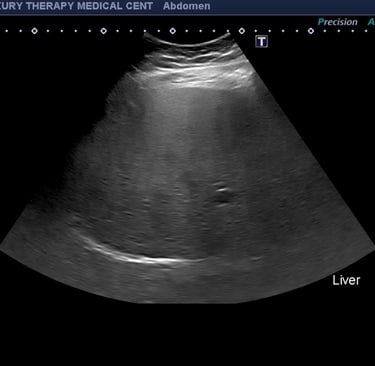

Cómo se detecta el hígado graso

El ultrasonido abdominal es una de las pruebas más comunes y efectivas para detectar el hígado graso. Este examen es:

En el ultrasonido, un hígado graso suele aparecer más brillante o hiperecoico en comparación con el tejido hepático normal.